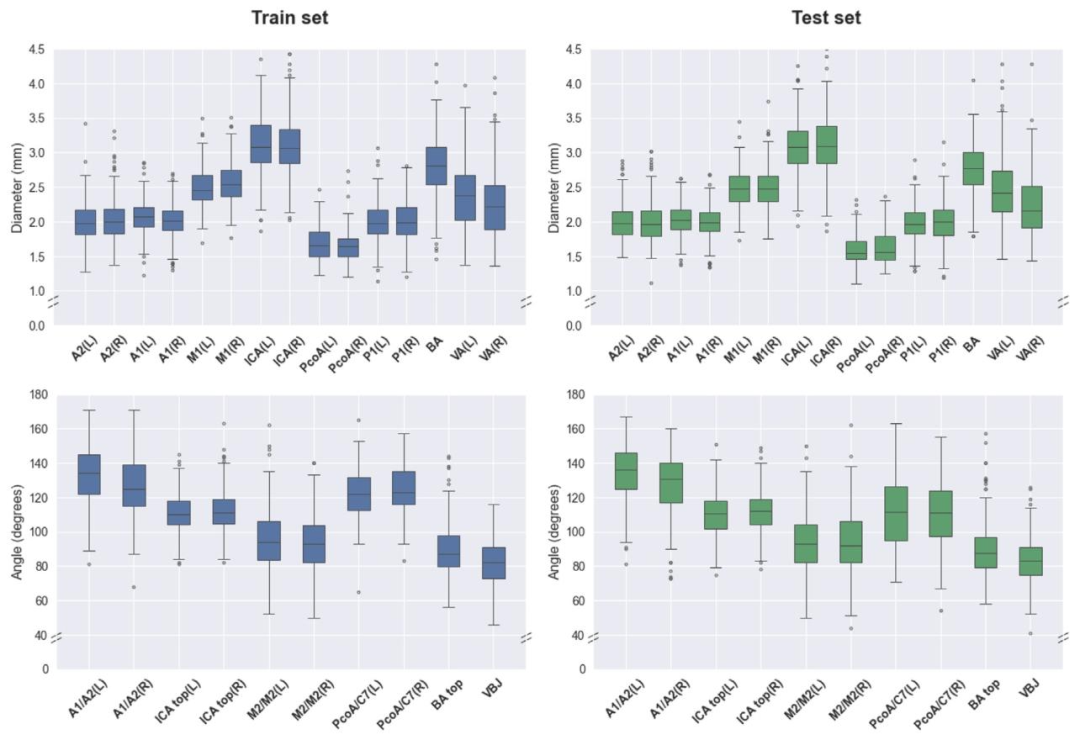

Fig. 4. Distribution of training and test cases for Task 2. Upper: artery diameters. Lower: bifurcation angles. A2 = A2 segment of the anterior cerebral artery (ACA); A1 = A1segment of the ACA; M1 = M1 segment of the medial cerebral artery (MCA); M2 = M2 segment of the MCA; ICA = internal carotid artery; C7 = C7 segment of the ICA; PcoA =posterior communicating artery; P1 = P1 segment of the posterior cerebral artery (PCA); BA = basilar artery; VA = vertebral artery; VBJ = vertebrobasilar junction.

图4. 任务2训练集和测试集的分布 上:动脉直径 下:分叉角度 A2=大脑前动脉(ACA)A2段;A1=大脑前动脉A1段;M1=大脑中动脉(MCA)M1段;M2=大脑中动脉M2段;ICA=颈内动脉;C7=颈内动脉C7段;PcoA=后交通动脉;P1=大脑后动脉(PCA)P1段;BA=基底动脉;VA=椎动脉;VBJ=椎基底动脉连接处。